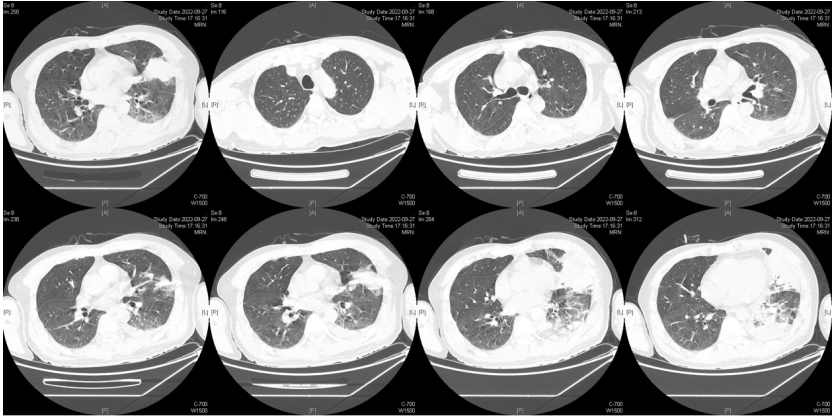

由于厌氧菌培养非常困难,既往我们对厌氧菌的认知仅限于在消化道定植,对其致病机制以及何种情况下致病并不非常清楚。厌氧菌定植于皮肤黏膜,是一种内源性微生物,感染发生率高,可导致严重、致死性感染。由于标本采集和转运的特殊性,使厌氧菌难以分离;加之其培养困难,体外生长慢,所以既往很难识别。厌氧菌在治疗方面存在一定挑战,如往往混合多重感染,且易产生耐药,也会因治疗延迟导致治疗失败。随着近10年来NGS技术的应用和普及,我们对厌氧菌的认识得以提升。常见的致病厌氧菌分为革兰阳性球菌、革兰阴性球菌、革兰阳性非芽孢杆菌、革兰阳性芽孢杆菌以及革兰阴性杆菌(表1)。革兰阳性非芽孢杆菌中可能致病的是放线菌,例如龋齿放线菌参与龋齿的发病过程。革兰阳性芽孢杆菌往往具有致病性,其中产气荚膜杆菌、艰难梭菌/难辨梭状芽孢杆菌、肉毒杆菌/肉毒梭菌、破伤风梭菌/杆菌具有强致病性。革兰阴性杆菌中的拟杆菌属对青霉素类药物具有很强的耐药性,易致青霉素治疗失败。临床中我们与厌氧菌的接触逐渐增多,对其特点也会愈发熟悉,对于临床诊断和治疗也会有所帮助。在NGS报告中通常会将检出的厌氧菌列为“C类”,定义为致病性C类—呼吸道正常微生态菌群,一般不导致感染。但当患者存在误吸风险时,需关注厌氧菌引起肺脓肿的可能。此时就需要针对患者的危险因素、临床表现、影像学、病原学以及气管镜下特点等进行综合分析。微小单胞菌最早是通过培养进行鉴定。瑞士2015—2022年132例病例报告的培养鉴定结果显示,血液中检出微小单胞菌37例(28%),肺内(肺脓肿、脓胸)检出29例(22%),总体病死率较低(5.3%)。国内周华教授团队开展的一项回顾性研究分析了2019年1月至2020年7月经病理活检和mNGS诊断的5例与微小单胞菌相关的慢性肺脓肿患者。患者的平均病程为6.5个月,共同特征是口腔卫生差,有酗酒史,且CT表现为边界不规则的高密度团块状实变影,并且在病灶中间可见液化性坏死,但没有发现气液平面或空腔,所以前期易被误诊为肺癌。下图1是该研究报告中病例3的肺部CT表现。时间点1:首次就诊时,左下叶可见团块状肺不张,伴周围磨玻璃样渗出病变,中心坏死不明显,可见细小空气囊泡影。时间点2:发病8个月时,可见大面积肺实变,增强CT示病灶内有液化坏死和小空洞。时间点3:经过3个月的有效抗厌氧菌治疗,病灶明显缩小,遗留空洞和纤维增殖病灶。图2是病例4的肺部CT表现。时间点1:患者首次就诊时,右上叶可见肿块样肺部实变影。时间点2:发病8个月时增强CT,可见实变明显增大,病灶内出现液化坏死。时间点3:经过3个月的有效治疗,病灶明显缩小,有残留空洞和纤维瘢痕样病变。由于通过影像学鉴别该病与肺癌具有挑战性,所以5例患者都接受了支气管镜检查和CT引导下经皮肺活检。5例患者经组织活检或支气管肺泡灌洗液(BALF)标本mNGS检测到微小单胞菌。病例: 女性, 67岁, 主诉"咳嗽咳痰2个月"。现病史:2个月前,患者家属感染新冠病毒(家属新冠抗原阳性)之后,患者出现咳嗽咳黄脓痰,无痰中带血及痰液拉丝,痰无臭味,无胸闷气短及胸痛,无咽痛咽痒,无鼻塞流涕。6月9日于当地市医院住院,住院期间出现发热,体温最高38.6℃,无寒战,查新冠病毒核酸阳性,予先诺特韦/利托那韦片口服治疗。查胸部CT见左肺上叶软组织影,左肺上叶炎症。诊断肺脓肿,予头孢唑肟联合莫西沙星,治疗后复查胸部CT(6月26日)病灶较6月9日明显吸收好转。6月14日气管镜检査见左肺上叶支气管开口狭窄,见大量脓性痰液堵塞支气管开口(病原学结果家属无法提供)。6月30日办理出院后仍有咳黄脓痰,无发热畏寒,口服止咳化痰药物,未使用抗生素。7月30日复诊胸部CT见左肺上叶异常密度较前增大。8月2日再次于当地市人民医院住院。8月4日气管镜检查: 左肺上叶黏膜肿胀肥厚, 管腔狭窄, 见大量白色干酪样分泌物涌出, 支气管镜不能进入。内科予莫西沙星静滴治疗10天, 外科予莫西沙星联合哌拉西林他唑巴坦静滴9天。复查胸部CT见病灶较前进展, 且右肺出现新发感染病灶。病程中患者饮食可, 睡眠差, 二便正常, 体重减轻5 kg。既往对阿莫西林过敏, 表现为口服阿莫西林后全身皮疹。否认嗜酒史及吸烟史。入院后胸部增强CT可见病灶内液化坏死,同时伴有小的空气囊泡影(图3)。患者有胸痛症状。气管镜检查发现气道内有痰栓或黏液栓阻塞征象(图4)。灌洗液tNGS结果回示:微小单胞菌(序列数2762),巨细胞病毒(序列数171),副流感病毒(序列数79),EB病毒(序列数61)。考虑病毒不会导致气道内如此改变,但由于微小单胞菌属于常见口腔定植菌,此时也不能完全确定微小单胞菌是否为引起感染的主要责任病原体。8月24日起予莫西沙星0.4 g qd ivgtt+哌拉西林他唑巴坦4.5 g q8h ivgtt。经过上述治疗,患者局部病灶有所吸收,但整个肺叶并无明显改善(图5)。气管镜检查仍然发现气道内有较黏稠的黏液栓阻塞气道开口(图6)。治疗经过:气管镜下予以局部冲洗,再次送检tNGS。9月7日结果回示:微小单胞菌(序列数6464),较前明显增多;副流感病毒(序列数998),EB病毒(序列数331)。9月9日起调整治疗方案为美罗培南1 g q8h。9月12日复查患者胸部CT,可见肺通气部分改善,肺组织内实变较前吸收(图7)。第三次气管镜检查仍可见少量痰栓嵌塞在远端支气管开口(图8)。患者此后转入医联体医院继续抗感染治疗。病例2:女性,54岁。主诉:咳嗽咳痰2个月,发热1周。现病史:入院2个月前,患者在西南地区旅游时感冒,出现咳嗽咳痰,白痰为主,量多,无胸痛,无发热,无痰中带血,咳时气短。于河北某诊所间断输液治疗14天(具体不详),期间口服中药治疗,症状未缓解。入院3周前(2023-09-07)就诊于当地县医院,查胸部CT提示右肺炎症,静脉滴注氨曲南、左氧氟沙星、氨溴索治疗1周,症状未缓解。2023年9月14日复查胸部CT显示右肺炎症较前加重,于当地中心医院住院。动脉血气分析:pH 7.43,PaCO2 38.4 mmHg,PaO2 67 mmHg,SaO2 94.2%;血沉90 mm/h;生化:白蛋白35.3 g/L;CRP 82.7 mg/L;血常规:WBC 9.75×109/L,NEU 6.83×109/L,HGB 104 g/L。静脉滴注莫西沙星。入院10天前,行肺穿刺活检,病理回报为少量肺组织及纤维结缔组织,炭末沉积,较多中性白粒细胞、淋巴细胞及浆细胞浸润,伴脓肿形成;肺穿刺mNGS结果回报:微小单孢菌(序列数2650),鲍曼不动杆菌(序列数17),人类疱疹病毒4型(序列数60),人类疱疹病毒7型(序列数5),文氏密螺旋体(序列数4337),解卵磷脂密螺旋体(序列数1121),齿垢密螺旋体(序列数698)。调整抗生素为头孢哌酮舒巴坦2 g q12h。入院1周前,出现发热,体温最高38.5℃,不伴寒战,咳嗽咳痰无加重,无咯血;复查血常规、PCT、CRP均明显增高(未见报告单);复查胸部X线提示右肺炎症范围增大,右侧胸腔积液。更换抗生素为哌拉西林他唑巴坦4.5 g q8h。4天前,支气管镜下见右肺下叶背段支气管略狭窄,黏膜水肿,可见脓性分泌物溢出。BALF革兰染色查见革兰阴性杆菌,抗酸染色、霉菌未见异常,培养未回报。患者体温逐渐降至正常,咳嗽咳痰有所减轻,复查胸部CT提示右肺高密度影,右侧胸腔积液较前增多。为求进一步诊治来我院就诊被收入院。既往甲状腺功能减退病史5年,目前口服优甲乐治疗,监测甲状腺功能指标在正常范围。20年前因宫外孕行手术治疗。2023年10月8日胸部CT示胸膜下斑片状坏死,纵隔窗可见微小空气囊泡影及密度不均匀液化坏死(图9)。治疗:9月28日至10月13日莫西沙星0.4 g qd ivgtt+哌拉西林他唑巴坦钠4.5 g q8h ivgtt。最终患者病灶吸收好转并顺利出院。患者男性,42岁。主因间断咳嗽、咳痰1月余,左侧胸痛、气短2天入院。现病史:入院前1月余(2022-07-19),患者无明显诱因出现咳嗽,咳白痰,痰中有少量鲜红色血丝,左侧胸痛(为钝痛),深吸气后加重,就诊于当地医院。完善肺动脉CTPA:示左上肺动脉舌段分支局部管腔可见线条样低密度充盈缺损,考虑肺栓塞;左肺上叶实性病变伴不均匀强化,性质待定,部分为肺梗死改变可能,纵隔多发稍大淋巴结,性质待定;右肺下叶后基底段可见一不规则实性结节,边缘可见多发毛刺,直径约0.7 cm。当地医院考虑肺栓塞不除外,肺部感染?右肺下叶结节,予莫西沙星抗感染,低分子肝素抗凝,乙酰半胱氨酸化痰。完善CT引导下肺穿刺活检,病理示:肺泡腔扩张伴上皮轻度增生,肺泡间隔纤维组织增生伴散在炎细胞浸润,未见恶性病变。院外规律应用甲磺酸艾多沙班60 mg bid抗凝,先后间断应用左氧氟沙星0.5 g qd、头孢类抗生素(具体药物、剂量不详)抗感染。患者仍有间渐咳黄白痰,量不多,痰中有少量鲜红色血丝;无畏寒、发热、胸痛、夜间阵发性呼吸困难症状,无尿少、双下肢水肿,无口干、咽干,无牙齿成片脱落,无晨僵、关节肿痛,周身无皮疹,无盗汗乏力。2天前(2022-09-16)患者无明显诱因再次出现左侧胸痛,疼痛剧烈,深吸气、咳嗽及改变体位时加重,伴气短,就诊于我院急诊。完善肺动脉CTPA:肺动脉主干及其各叶段分支未见明显充盈缺损,左肺上叶舌段团块影,最大截面约7.6 cm×5.3 cm,边界不清,周围可见晕征;增强扫描不均匀强化,邻近胸膜增厚,性质待定,建议穿刺活检;纵隔及左肺门多发淋巴结显影。血细胞分析:WBC 11.09×109/L,NEU% 80.8%,NEU 8.95×109/L;CRP 54 mg/L,PCT 0.07 ng/ml。患者自发病以来,精神状、食欲及睡眠均一般,大小便正常,体重下降5 kg。2022年9月14日外院胸部增强CT:胸膜下楔形的影像学表现可见少量小气泡囊以及液化坏死病灶(图10)。初始考虑肺部肿瘤及肺栓塞。经过初步抗感染及抗凝治疗,患者病情无缓解,2022年9月27日患者突发胸痛,下肺影像加重并且出现脓胸(图11)。行胸腔穿刺并将脓液送检mNGS,结果回报:牙龈卟啉单胞菌(序列数3)。尽管序列数很低,但考虑是脓肿穿刺结果,因此考虑该菌致病可能。抗厌氧菌治疗:9月16-28日莫西沙星0.4 g qd ivgtt,9月23日-10月12日美罗培南1 g q12h ivgtt,9月28日-10月8日万古霉素1 g q12h ivgtt,10月13-18日莫西沙星0.4 g qd ivgtt+甲硝唑0.5 g tid ivgtt。患者肺脓肿的整体治疗时间约为3个月,病灶逐渐吸收,最终形成一些纤维索条影(图12,图13)。1年后复查病灶基本吸收(图14)。图14 1年后复查胸部CT(2023-08-08)微小单胞菌和卟啉单胞菌这两种厌氧菌在临床中需要引起重视,它们容易引起肺脓肿/脓胸。2024年国内学者Li Yao等在Diagn Microbiol Infect Dis 杂志发表了一篇牙髓卟啉单胞菌感染所致肺脓肿的病例报告,文章也提到在胸水或肺组织活检中,通过mNGS同时检出了微小单胞菌和卟啉单胞菌感染引起的肺脓肿。文章还回顾总结了既往发表的厌氧菌感染引起肺脓肿的病例,2010年报道的是1例脑脓肿患者,2019年报道1例脑炎患者,2022年报道1例脓胸伴呼吸衰竭患者。3例患者预后都比较好,可见厌氧菌亦可导致肺外多部位感染。对于厌氧菌所致肺脓肿的诊断及其引起的脓胸,目前的文献报道仍然较少,我们对它们的认知也有限,因此也提醒大家关注相关疾病的诊断和治疗。我们也已将本研究小组8例微小单胞菌所致肺脓肿的系列病例的研究结果发表(Front Cell Infect Microbiol, 2024, 14: 1416884),可供需要的同行参考。对于厌氧菌感染,我们需要提高警惕。厌氧菌往往在口咽部定植,其引起的脓肿/感染往往多为亚急性或慢性起病。患者通常有发热、胸痛症状,脓肿会逐渐进展。由于厌氧菌与人体本身是一种长期共生的关系,人体对厌氧菌的免疫识别可能处于较低的防御反应状态,所以会形成一个亚急性或慢性的发病过程。通常情况下,因厌氧菌的菌群发生了移位,从卫生条件不好的口腔扩展到相对无菌的肺内,同时开始增殖,由此可能导致感染。因此,对于酗酒以及口腔卫生非常差的人群,我们要重视对其风险因素和病史的排查。患者就诊时可能病情并不重,有胸痛或咯血,很容易误诊为肺部肿瘤,往往在这种情况下进行肺穿刺或气管镜检查,mNGS可以发现较大序列数的厌氧菌。但在mNGS检出厌氧菌后的诊断过程中又容易形成误判——究竟是致病菌,还是定植菌?此时结合患者其他病史和影像学特点(有脓肿/痰栓形成,微小空气气囊泡影),可能提示厌氧菌感染。然而,厌氧菌感染在病原学和影像学诊断方面仍然存在诸多困难,极易漏诊和误诊。微小单胞菌感染患者在气管镜下可以看到典型的脓性分泌物嵌塞气道,导致气道阻塞,也会造成远端气道和肺泡引流障碍。所以,及时处理气道内痰栓,改善引流,可能是使患者获得良好预后的关键。厌氧菌肺脓肿的吸收比较缓慢,抗感染的疗程也比较长,需要在后期诊疗过程中密切随访和观察患者对治疗的反应以及耐药等问题,及时调整治疗方案,适当延长疗程。